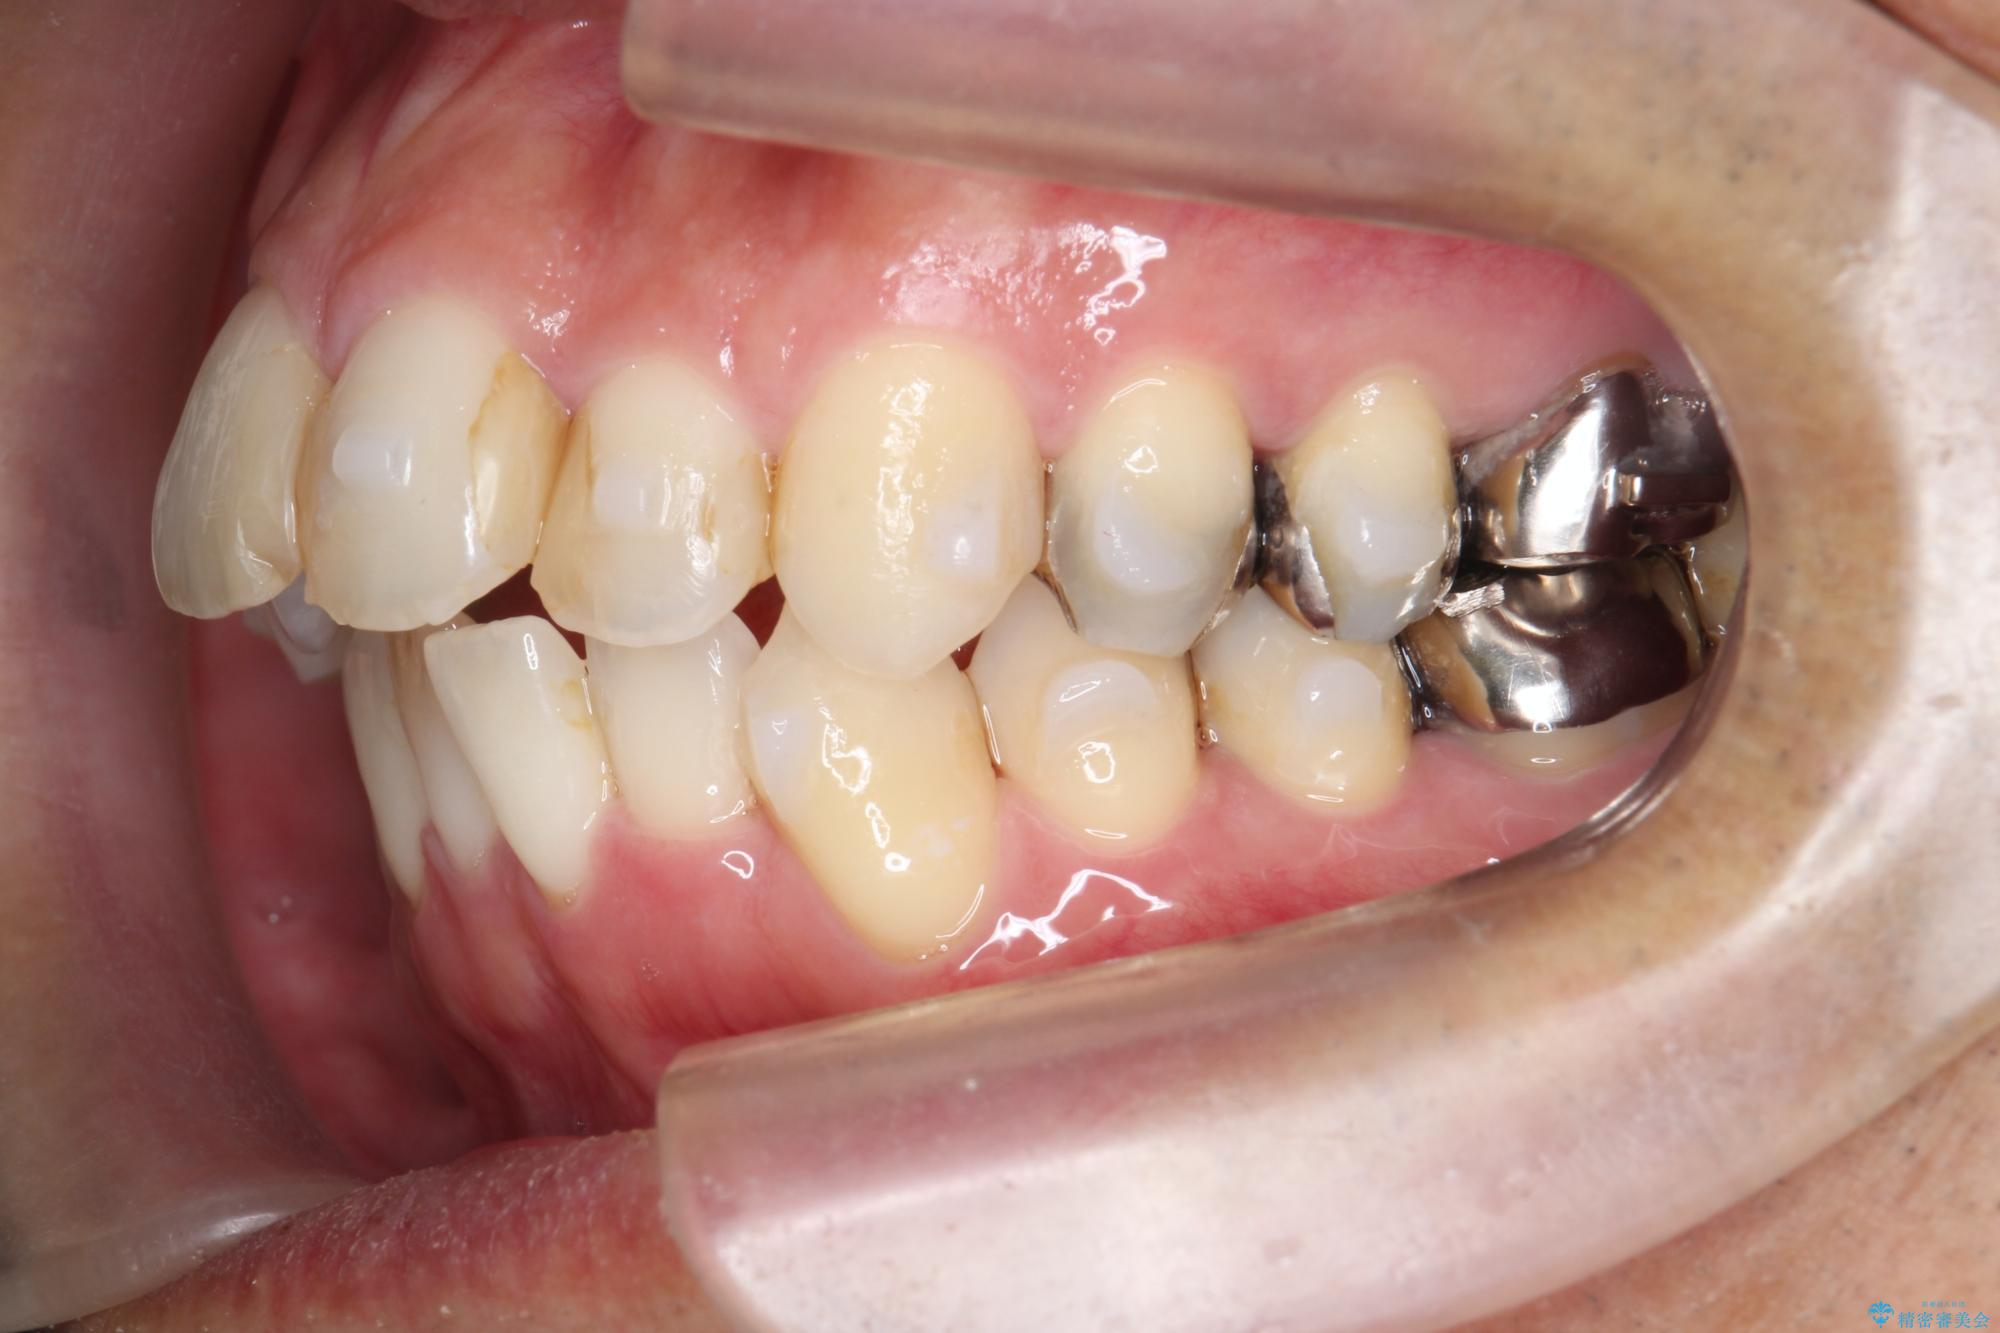

矯正と虫歯のセラミック治療 総合歯科治療の実践

- 突き出た前歯の角度の改善と虫歯治療の改善を求めて来院されました。

虫歯を除去したのち、マウスピース矯正治療を行い、歯並びやがたつきを改善したのち、セラミックに置き換えることで審美性の向上を計画します。